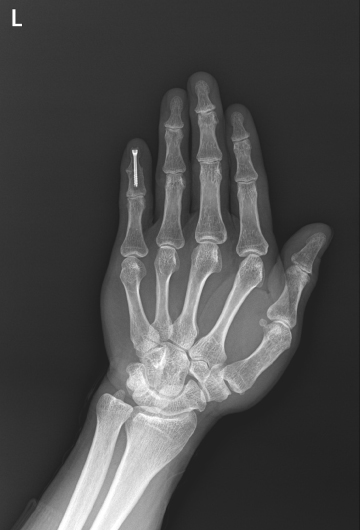

수술후

2022.03.25